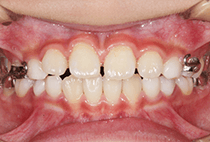

40代女性の患者さま。

グラグラする歯と乱れた歯並びが気になりご来院されました。

「見た目も気になるし、このまま歯が抜けるかも…」そんな不安を抱えていらっしゃいました。

治療は3ステップで進めました。

矯正後は、かぶせ物の治療もあわせて行い、「しっかり噛めて、見た目も自然で美しく」を達成できました。

しっかり噛めるようになったことで頬のコケ間や口元のゆるみが改善され若々しく引き締まった印象になりました。

そして何より、治療終了から15年後も歯ぐき・歯並びともに安定し、健康的で美しいお口元をキープされています。

グラグラする歯と乱れた歯並びが気になる

叢生、重度歯周病

40代女性

矯正治療1年、歯周治療3ヶ月

12回

唇側矯正、審美治療、歯周病治療

矯正:955,900円+毎月調整量:6,050円

歯ぐきの炎症をしっかり改善(歯周病治療)してから、装置セット。

歯並びと噛み合わせを整える(表側矯正・1年間)。

見た目と機能の仕上げ(審美的なかぶせ物)。

治療前

治療後

治療終了から15年後も歯ぐき・歯並びともに安定し、健康的で美しいお口元をキープされています。